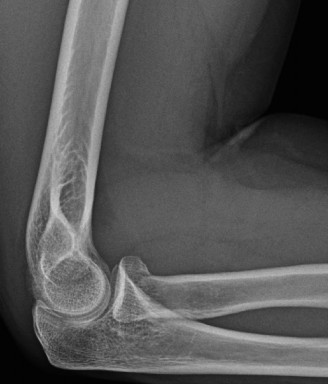

Treat a patient with infected total shoulder arthroplasty? CASE 21 A 70-year-old, right-hand-dominant female presents to clinic complaining of 4 years of gradually worsening chronic right shoulder pain and stiffness. She says the pain is worse at night and with any range of motion, denies a history of trauma, pain in other extremities, or numbness or tingling of the right upper extremity. She notes that her mother suffered from rheumatoid arthritis that affected her shoulder. Physical examination reveals decreased muscle bulk over the right supra- and infraspinatus fossae compared to the contralateral side, limited active and passive ROM, marked weakness with external rotation, and 4+/5 strength with shoulder abduction. X-rays of the right shoulder are shown in Figures 2–58 and 2–59.

Figure 2–58

Figure 2–59

What is the most likely diagnosis?

- Rheumatoid arthritis involving the right glenohumeral joint.

- Frozen shoulder (adhesive capsulitis)

- Rotator cuff tear arthropathy

- Osteoarthritis involving the left glenohumeral joint

The correct answer is (C). Rotator cuff tear arthropathy consists of a combination of rotator cuff insufficiency, glenohumeral joint degenerative changes, and superior humeral head migration. It is more common in women and also more often found on the dominant side. The patient’s clinical examination with weakened external

rotation and muscle atrophy signaling incompetent supra- and infraspinatus muscles point to rotator cuff insufficiency, and her plain films reveal narrowed glenohumeral joint space as well as superior migration of the humeral head. Choice D is incorrect because, while radiographs would show narrowing of the glenohumeral joint space, they would also likely show numerous osteophytes and posterior wear of the glenoid. Choice B is incorrect because, while adhesive capsulitis does present as decreased active and passive range of motion, the patient’s constellation of symptoms pointing towards rotator cuff insufficiency along with the radiographs make cuff tear arthropathy the more likely choice. Finally, Choice A is incorrect because even though she has a positive family history of rheumatoid arthritis, it is less likely to present only in a single joint. Also, rheumatoid arthritis on radiography appears more as an erosive process without the characteristic superior migration of the humeral head.

Which of the patient’s radiographic findings is most indicative of chronic rotator cuff insufficiency?

- Superior migration of the humeral head

- Narrowed glenohumeral joint space

- Subchondral sclerosis

- Osteopenia of the proximal humerus

The correct answer is (A). Superior migration of the humeral head would be most indicative of chronic rotator cuff insufficiency associated with cuff tear arthropathy, as it is a direct result of the inability of the rotator cuff tendons to help maintain the humerus in its normal position. Acetabularization of the undersurface of the acromion is commonly associated with superior migration of the humeral head found in rotator cuff tear arthropathy, and can be assessed using the Hamada classification, which is based on measurements of the acromiohumeral interval on radiography (Table 2–8). Choices B and C are incorrect because, while narrowed glenohumeral joint space and subchondral sclerosis are associated with rotator cuff arthropathy on radiographs, they indicate degenerative joint changes rather than chronic rotator cuff insufficiency. Choice D is incorrect because it is not a specific sign of rotator cuff arthropathy.